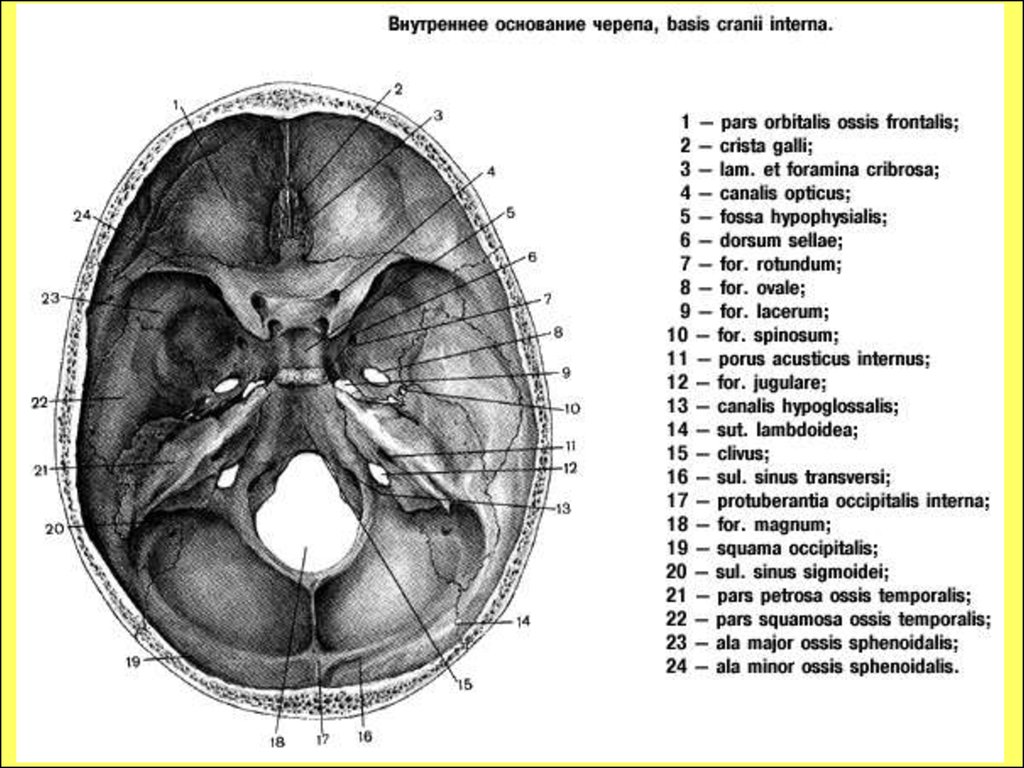

Анатомические детали: Фотографии топографии черепа с нижнего вида